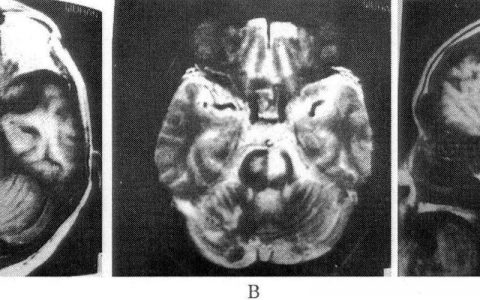

病史和体格检查提示可能是脑血管意外。在进行任何治疗干预之前,必须进行紧急CT扫描以排除出血。在此例中,我们被告知CT检查正常,这意味着未见出血。鉴于临床高度怀疑卒中,你的注意力应该集中在缺血性病因的可能性上。然而,重要的是要记住,缺血性梗死通常在最初的扫描中是不可见的,特别是如果在症状出现后的几个小时内进行扫描。组织型纤溶酶原激活剂(tPA)是一种溶栓药物,鉴于患者没有任何明显的溶栓治疗禁忌证,因此该患者的下一步治疗是最好的。tPA治疗已被证明在急性缺血性卒中的治疗中非常有效,尤其是在症状发生后3小时内给药。然而,这种治疗方式有出血的风险。